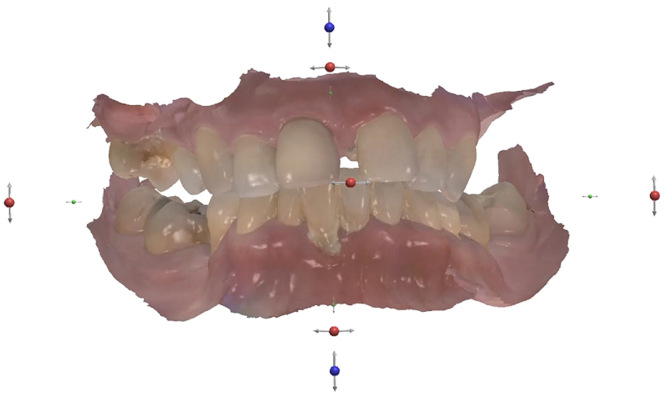

Before surgery, an intra-oral scanner was employed to acquire the digital data for the design of the temporary prostheses (Fig. 7). The teeth were digitally removed, and digital prostheses were created. The data of the virtually constructed prostheses was subsequently transmitted to a milling machine for the fabrication of monolithic PMMA prostheses.